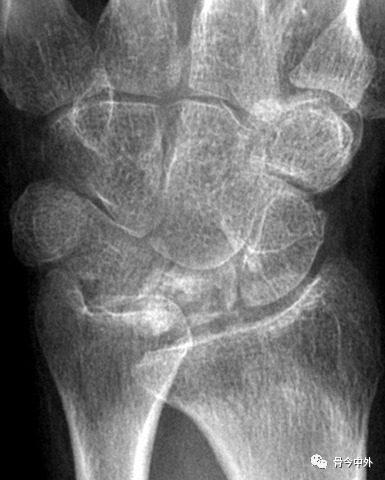

图1 成人期腕关节正侧位及舟骨蝶位片。1.舟骨;2.月骨;3.三角骨;4.豆状骨;5.大多角骨;6.小多角骨;7.头状骨;8.钩骨;9.桡骨茎突;10.尺骨茎突;11.第一掌骨基部。

图2 成人期腕关节正侧位及舟骨蝶位片。1.舟骨;2.月骨;3.三角骨;4.豆状骨;5.大多角骨;6.小多角骨;7.头状骨;8.钩骨;9.桡骨茎突;10.尺骨茎突;11.第一掌骨基部。